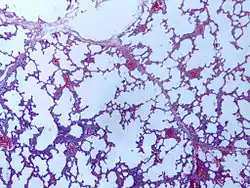

![]() | Emphysema | Micrograph of empysema lung showing dialated, large alveoli separated by thin septa. Some septae are ruptured and appear to be floating in the alveloar spaces. Grossly emphysematous lung appears pale and voluminous. | Category: Histopathology of pulmonary emphysema | Emphysema |